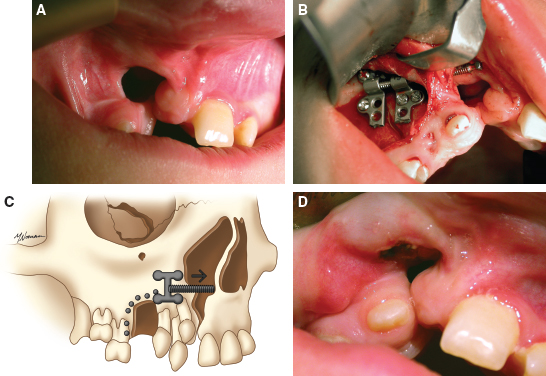

70 ○ Patient selection for alveolar transport distraction osteogenesis and its ultimate success involve patient motivation, parent and patient commitment to the procedure and postoperative course, and excellent oral hygiene. ○ Preoperative planning using three-dimensional imaging and models to execute the projected movements is vital to confirm ultimate segment positioning and stability. ○ Local tissue health and integrity with enough attached gingiva for final “docking” of the distracted segment and bone grafting of the defect is necessary before initiating distraction. ○ The reconstruction team consists of a surgeon, an orthodontist, and a restorative dentist (prosthodontist) who agree on the plan and timing for distraction. ○ Simultaneous anterior maxilla and piriform distraction can be achieved through distraction of a larger dentoalveolar segment, thus augmenting these regions, with or without grafting. Management of the alveolar cleft defect (ACD) has often been a challenging aspect of the comprehensive management of patients with orofacial clefts. The ACD results from intentional delay in treatment or failed attempts at repair during primary cleft lip or palate surgery. Typically, ACDs result in a collapsed, disunited arch with unsupported lip, nasal, and dental elements. The concomitant oronasal fistula (ONF) contributes to sinonasal inflammation, drainage, and periodontitis. Therefore repair of the osseous defect and closure of the fistula are considered important aspects of complete cleft management. Fig. 70-1 A, Right unilateral cleft with wide, disparate alveolar segments. B, Right unilateral cleft with deficient soft tissue and a wide bony defect. Repair of the ACD has a long history in cleft care. The goals for adequate treatment include1,2: Attempts at ACD closure by performing gingivoperiosteoplasty at lip repair have been met with varying results, oftentimes necessitating future formal repair with bone grafts. The timing of ACD repair also has been controversial. Primary osteoplasty, with placement of autogenous bone at or near the time of initial lip repair, has been both condemned and championed. Many results have been less than ideal, again with the need for further bony augmentation of the alveolar segment.3–5 Secondary osteoplasty of the ACD is considered the treatment of choice for many cleft teams, principally because it is predictable and achievable, satisfying the goals of repair as stated previously. Early secondary osteoplasty, as advanced by Boyne and Sands6 as well as others, attempts to graft the ACD before eruption of the permanent incisors.7,8 Delayed secondary osteoplasty has been shown to be effective and predictable for most children when it is performed before the complete root formation of the adult canine tooth, around 10 to 12 years of age.9,10 Delayed secondary osteoplasty is usually performed in conjunction with preparatory orthodontics and after some orthopedic manipulation to optimally position the cleft segment. However, a significant number of patients experience failed bone graft procedures, have very wide defects with collapsed cleft segments, or have significantly scarred ACDs with questionable soft tissue covering, all of which make further attempts at bone grafting rather dubious and unsatisfying. This is aptly termed recalcitrant ACD (Fig. 70-1) and is especially challenging in particular circumstances: a lack of healthy unscarred mucogingival tissue lining the ACD, deficient alveolar bone height and width against which the graft must be placed, older patients with decreased bony healing potential, and the presence of compromised dentition or prostheses with little bone support.11 Recently, distraction osteogenesis (DO) has been developed for application in the craniofacial region. Smaller regional areas of the facial skeleton have been distracted to optimize functional and aesthetic units for future orthopedic or orthodontic correction, grafting procedures, or prosthodontic rehabilitation. In 1905, Codivilla12 initially described the concept of DO to lengthen a femur, correcting a limb length discrepancy. In the 1950s, this application was more widely applied to orthopedic limb lengthening. The landmark research into this technique by Ilizarov13 looked at the development of distraction techniques, devices, and rates on bone formation. He developed the technique on canine long bones and then applied the protocol to human patients, pioneering many of the concepts of DO, including recommendations on latency, distraction rate, and distraction rhythm. In 1992, McCarthy14 applied DO to the unilateral mandibular deficiency found in hemifacial microsomia. He lengthened the affected mandible in children using an external fixation device, which allowed calibrated distraction between external pins holders. At the completion of the distraction phase, the mandibles were stabilized for a mean period of 9 weeks. DO of the midface region has been performed by devices categorized as internal or external devices. Several maxillary DO devices have been used to advance the maxilla through either various osteotomies at the LeFort levels or segmentation of the maxilla.15 These procedures are discussed in Chapters 73 and 74. To achieve maxillary arch widening, Bell and Epker16 used a DO technique of rapid palatal expansion with a tooth-borne expander, increasing the transverse dimension of the maxilla after osteotomies had been performed. Guerrero and Bell17 further developed these techniques, using incremental expansions of 1 mm every other day, up to a total of 10 mm, to obtain significant transverse expansion of the arch. This concept was applied to the alveolar segment by Chin and Toth,18 who looked at regenerating alveolar bone after trauma using an internal distraction device with a transmucosal activation screw. Block and Baughman19 further applied DO to the vertically deficient alveolar segment, increasing bone height before implant placement. Simultaneous secondary bone grafting was performed in many of these cases after final alveolar segment distraction. Use of alveolar distraction is now widespread for preprosthetic manipulation before rehabilitation.20 Cleft alveolar distraction has been performed and studied by Liou et al,21 who used various osteotomies and appliances to approximate cleft segments, narrow the ACD, and improve arch dimension. Others also have applied DO to correct various cleft-related problems, such as a narrow or collapsed maxillary arch and a wide ACD with insufficient soft tissue, and to prevent bone grafting an ACD.22–25 Distraction has become an important tool in the management of particularly difficult or recalcitrant ACDs, discussed later in detail. Several indications for alveolar transport DO exist. A very wide ACD may preclude a bone graft if soft tissue and alveolar bone are deficient (see Fig. 70-1). A patient who has had a previous failed bone graft may be considered for transport DO to achieve the goals of standard alveolar cleft surgery (Fig. 70-2). Older patients who have not been treated for their ACD may be candidates for transport DO to narrow the defect and thus require minimal secondary grafting, improving the success for prosthetic rehabilitation. Fig. 70-2 A, A failed primary osteoplasty with a persistent defect. The failed bone graft was done at age 1. The patient has a fistula and insufficient osseous support for dental structures. B, Partial osteoplasty of a bilateral cleft defect with failure of the graft on the patient’s right. C, A patient with a partial osteoplasty on the left and complete failure on the right side. Alveolar cleft defects are, by nature, multidimensional, and have different defect combinations including the anteroposterior, horizontal, and vertical dimensions. Depending on the specific defect, transport DO may be considered for definitive treatment or to address the largest dimensional deficiency, thereby improving the quality and quantity of alveolar bone. This will allow for an easier and minimal secondary bone graft procedure. This process is particularly applicable when treating vertical alveolar deficiency. Vertical alveolar DO may be considered to increase alveolar bone height after grafting and when planning placement of an implant for later prosthetic rehabilitation. Several contraindications to alveolar cleft DO exist. A surgeon should be wary of initiating alveolar DO for patients with clefts who have not been compliant in various aspects of their treatment. DO is a very labor-intensive process, requiring a great deal of cooperation from the patient and caregivers; therefore education is crucial before initiating treatment. Patients with active dental issues should have these addressed, with consideration given to optimizing oral health before surgery. Periapical disease should be eliminated to prevent infection during the distraction period. In patients younger than 10 years of age, the potential exists for damage to developing teeth and impairing the eruption pattern in the area of distraction. This needs to be thoroughly discussed with the patient and family beforehand. Indirectly associated with compliance are the patient’s general health and condition of the local tissues. If any concern exists related to these areas, avoiding this mechanically technical procedure and the potential subsequent complications of tissue breakdown and loss of the device may be prudent. Children who have poorly controlled chronic asthma or allergies, resulting in nasal obstruction and patterns of mouth breathing that increase oral tissue inflammation, may be prone to intraoral tissue compromise and breakdown. For these reasons, optimal intraoral health should be maintained through primary care and pediatric dental management. Once these concerns have been satisfied, then plans for distraction can be undertaken. Fig. 70-3 An acrylic model of a right unilateral cleft defect (X) demonstrating planned distraction of the alveolar segment (arrow). As with all aspects of comprehensive cleft care, management of the ACD benefits from a team approach. Preparing the patient and family for the various aspects of therapy is important before initiating alveolar transport DO. In addition, coordination of the team involved in perioperative management is essential. The patient’s pediatric dentist should be involved well before transport DO is considered to optimize oral health before surgery. Any carious lesions should be addressed and periodontal disease eradicated before the patient is assessed for surgery. Questionable or nonvital teeth should be treated before DO is begun to eliminate the possibility of infection jeopardizing the distraction process. Orthodontic consultation and management is important to address dental and arch discrepancies before the repair of the ACD, whether by conventional bone grafting or by movement of the alveolar bone using distraction. The arch may require expansion before formal repair of the alveolar cleft, and the orthodontist must be involved in the planning and management during distraction. Finishing dental and arch alignment is the orthodontist’s responsibility. Prosthodontic management of the patient may be required postoperatively for the replacement of missing teeth. This may involve the placement of crowns or bridges, or the surgical placement of implants if bone stock is adequate. The patient must appreciate that grafted bone must be completely mature before implants can be placed, a period of approximately 3 months.26 Consultation with the prosthodontist is important to evaluate the arch space and bone height that will be needed for prosthetic rehabilitation. Three-dimensional acrylic models (Fig. 70-3) are a great help to the treating team, patient, and caregivers who will be involved in the distraction process. Precise placement and activation of the device can be achieved and demonstrated. The caregivers need to be instructed in the cleansing and hygiene of the activation rod. Perioperative antibacterial mouth rinses (oral chlorhexidine) and oral antibiotics should be carefully reviewed and dispensed. Pain medications and dietary instructions will need to be adjusted based on individual patient needs. Most children will have adequate analgesia with ibuprofen, which may be administered before or after each distraction event, as indicated. It is important to instruct the patient and caregivers about the objectives of DO and to create realistic expectations for what can be achieved. Instructions for care may have to be given in stages and over several preoperative appointments to establish a thorough understanding before and during treatment. The patient and family need to appreciate that DO may not be able to completely correct the anatomic deficits. Further surgery, in a second stage, will be required to remove the distractor; at that time, the defect can be simultaneously augmented with additional bone graft if necessary. As in many ACD reconstructions, final and acceptable soft tissue coverage may be required in a separate procedure to provide adequate attached gingiva around the teeth and implants. Vital to the success of any intraoral surgical procedure, particularly around the dentition and any abnormal anatomy, is optimal soft tissue composition and health. Loss or limitation of healthy keratinized tissue around the dentition may compromise the general integrity of the periodontium, leading to further bone loss or predictable bony surgery in the future. Studies have demonstrated that patients with cleft lip or palate have more periodontal compromise in the cleft defect area, including loss of a zone of healthy keratinized tissue.27,28 Although loose (unattached) mucosa may serve as a temporary healing or covering measure, such as labiobuccal mucosa grafts placed during primary or early secondary osteoplasty, this does not serve well for periodontal integrity in the long term. If plans are made for segmental osteotomy or distraction of a cleft segment, healthy abutting transposed attached (keratinized) tissue, both palatally and labiobuccally, is preferable. Soft tissue inadequacies such as these are seen especially in older cleft patients who have undergone multiple procedures, resulting in compromised soft tissue in and around the alveolar cleft defect and dentition.29 If a lack of healthy soft tissue is determined during the evaluation process, then plans should be made to graft the area to provide this tissue. Autologous graft from the palate (preferred) or acellular dermis graft can be placed in the immediate defect area and periodontium.30 After a period of maturation, variably 8 to 12 weeks, when keratinization is complete and inflammation resolved, subsequent bony surgery can be undertaken. When juxtapositioning the alveolar segments during final distraction, flap elevation and coverage of the bone graft should be easier and final closure more predictable with appropriately healthy mucogingiva. Unilateral ACDs are more common and often have problems with significant asymmetry and excessive defect width. Although skilled interceptive orthodontics can often successfully align and position the lesser segment and narrow the defect width, occasionally the poorly positioned cleft segment will remain, with suboptimal soft tissue that would compromise, and potentially prohibit, orthodontic treatment. A typical case is illustrated in Fig. 70-4. This patient had a long history of cleft surgical procedures, as well as two phases of orthodontics. The ACD was still poorly positioned with extensively scarred soft tissue; the radiographs verified a significant bony defect width between the segments. This situation is difficult to correct with conventional orthodontic preparation and alveolar bone grafting; therefore distraction of the cleft segment, to narrow the defect by approximating the alveolar segments, will increase the success of a smaller bone graft. A single vector alveolar distractor was placed on the buccal aspect of the lesser segment after vertical osteotomy between the bicuspids and horizontal osteotomy, approximately 7 to 8 mm above the level of the root apices. The activating rod is oriented in a favorable position under the lip for easy access. Postdistraction photos demonstrate an alveolus more favorably positioned for bone grafting. Many alveolar distractors offer various distracting lengths (10 to 20 mm) and multiple options for plate and screw placement (Fig. 70-5). The device should be contoured to the alveolar surface so that activation will move the segment in the desired direction. Some distractors allow for orientation of the activation rod from 0 degrees (coaxial to the distractor) to 30 degrees to allow favorable rod positioning and access for daily activation. Minimal activation should be performed during the surgical procedure to prevent undue tension on the overlying soft tissue, which may tear and compromise vascularity. Two or three millimeters of activation, to confirm complete mobility of the osteotomized segment, will suffice at the time of distractor placement.